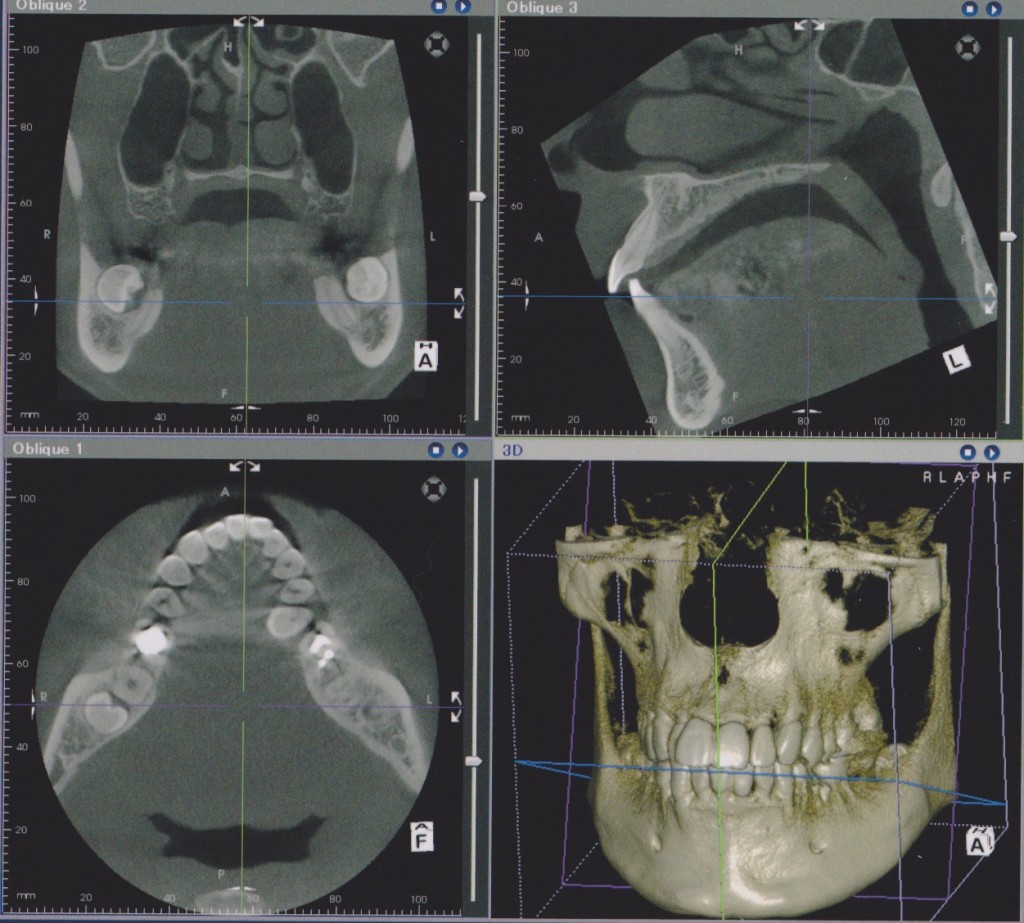

エックス線CT診断装置を導入いたしました。

この装置は今までの平面的なレントゲン写真ではなく、立体的に撮影し必要な場所の断面を見ることのできるものです。特に歯の神経の処置や歯周病の治療において歯の周囲の顎骨の様子が手に取るようにわかり、確実な診断の助けになります。